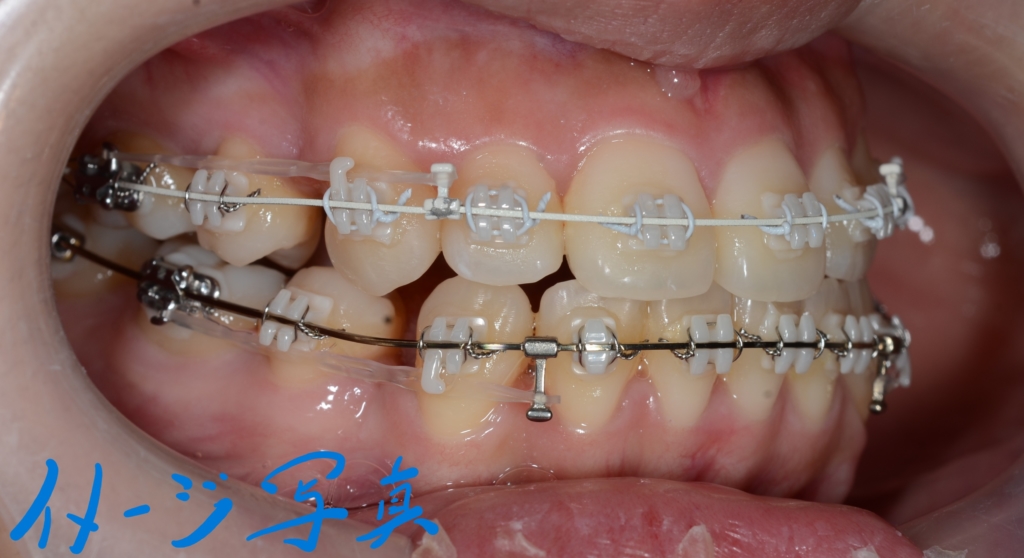

マルチブラケットシステム(ハーフホワイトtype)で矯正治療を開始。

前歯の乱れが解消され、きれいに並んだので、次のステップに入ります。

上下とも前歯を後方へ最大限に引っ込めて行きます

この方の写真が見つからないので、同じことをしている方の写真をイメージ写真としてあげています

【途中経過】 当初に抜歯をして出来たスペース分は、しっかりと引っ込めることが出来ました。

ただ、元の噛み合わせが出っ歯だったので、「出っ歯」が残ってしまいました。

そこで、アンカースクリューを追加して更に引っ込めることにしました。

上顎の口蓋の中央部に2本植立しました。

上顎のアンカースクリューにはPLAS & 奥歯の内側にはパラタルバーを付けて、上の歯列(歯並び全体)を出来るだけ後方へ引っ込めて行く「矯正力」を加えて、治療を再開しました。